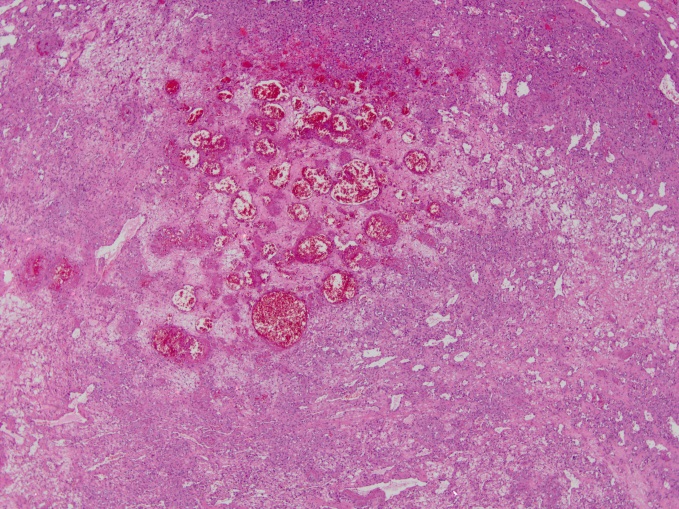

The excised tumor appeared gelatinous and histopathology revealed vascular channel proliferations with central myxoid changes. Staining was highly positive for CD31 and negative for CKAE1/3 and calretinin, which is highly suggestive of a vascular proliferative lesion of pure endothelial origin (Fig.8). Pericardial details included only mild chronic inflammation, and lung sections demonstrated subpleural fibroelastosis and peribronchial metaplasia.